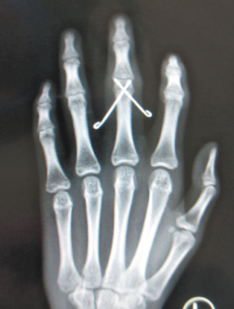

张医生赶紧安排手术行手法复位左中指近节指骨骨折,用2枚直径1.0mm钛克氏针电钻打入固定。术中透视骨折已复位,内固定在位良好。

张继朝医生介绍说:小鹿同学现在15岁,属于未成年人,尚在发育中,所以能不做切口就不做切口。做了切口后,后期容易出现疤痕增生、疤痕挛缩的情况,正常皮肤和疤痕生长的速度不一样,会影响美观,影响外形。像这种手法复位内固定,打完麻醉后,手法复位,复位后透视,骨折位置好,后期恢复都会不错。闭合打克氏针,有以下优点:用钢针固定,不经过关节,不影响手指活动。只留1mm的针点,等以后骨头长好后,钉子拔出来,这样手上也不会留疤。